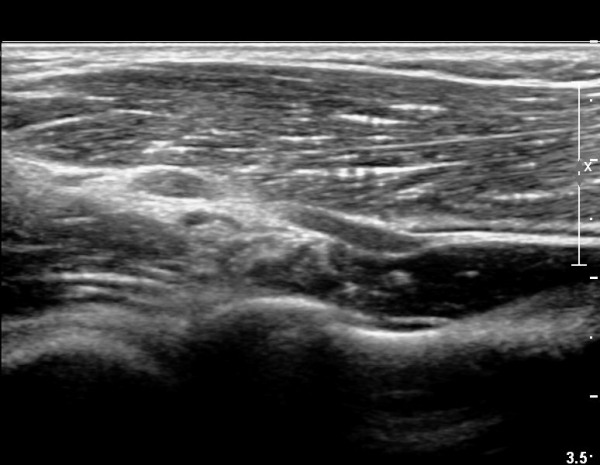

ŽÃËÀÚ¸¦ Á¶±Ý ´õ À̵¿ÇÏ´Ï Èİñ°£ ½Å°æÀÇ ºÎÁ¾ÀÌ ´Ù½Ã °üÂûµÈ´Ù(»çÁø 3).